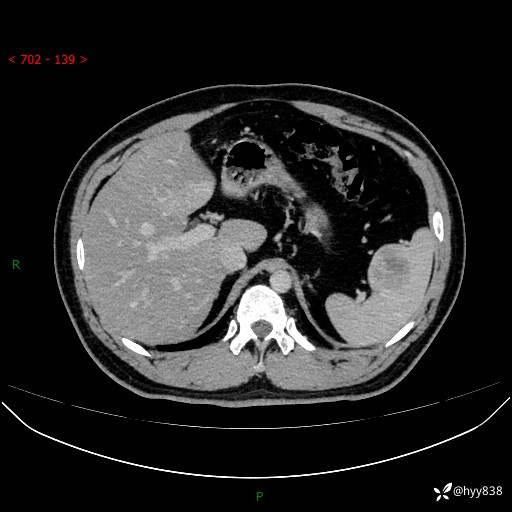

【患者信息】:31岁/男

【主诉】:超声发现脾脏肿物,为进一步诊治来我院,门诊以“脾脏占位”收入院

【检查】:上腹部CT平扫+增强